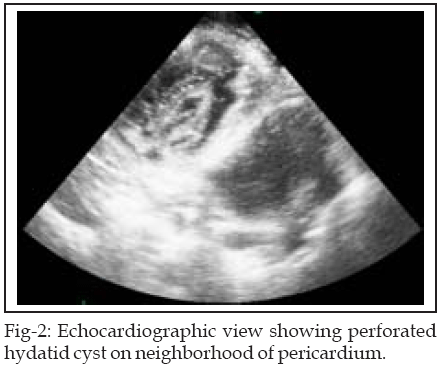

Chest radiograph taken on admission showed tension pneumothorax, mediastinal shift, and tracheal displacement (Fig-1). Echocardiography showed perforated hydatid cyst adjacent to pericardium (Fig-2). Electrocardiogram showed sinus tachycardia. The ultrasound scan confirmed a single 16-week viable fetus. Renal and hepatic function tests were normal. Indirect hemagglutination test for echinococcus was negative.

Pulmonary hydatid cysts are asymptomatic until they reach a large size and become complicated.2 A sudden rise in the intrapulmonary pressure is the usual precipitating factor in rupture of the cyst: the cause could be a trivial one such as coughing or sneezing, though sometimes it may follow an increase in intraabdominal pressure as in pregnancy. However rupture may occur spontaneously without any predisposing factor.5 The occurrence of tension pneumothorax because of the rupture of the hydatid cyst is a rare complication. The signs of tension pneumothorax include marked dyspnea, cyanosis, tachycardia and hypotension. The trachea is usually deviated to the contralateral side and the affected side of the chest demonstrates increased resonance to percussion and decreased air entry and breath sounds.6 In this case, chest radiograph and echocardiography were of great value in diagnosing the perforated pulmonary hydatid cyst adjacent to pericardium.